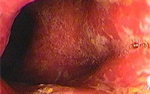

**溃疡性结直肠炎**

本病主要累及直肠、乙状结肠,亦可向上扩展致全结肠和回肠末端,以血性黏液便、腹痛、腹泻为主要症状。容易反复发病。

二、病理:病变早期,表现为黏膜充血、水肿, 黏膜脆弱呈点状出血,或自发性渗血;随着病变的发展,部分黏膜表面坏死脱落, 形成密集、细小、表浅的溃疡;病变进一步发展,黏膜大片坏死,形成大的溃疡。溃疡愈合后形成瘢痕,可致肠腔狭窄;由于深的溃疡的形成,黏膜上皮组织增生,形成息肉,称为“炎性息肉”或“假性息肉”,较小,大小一致,细长。